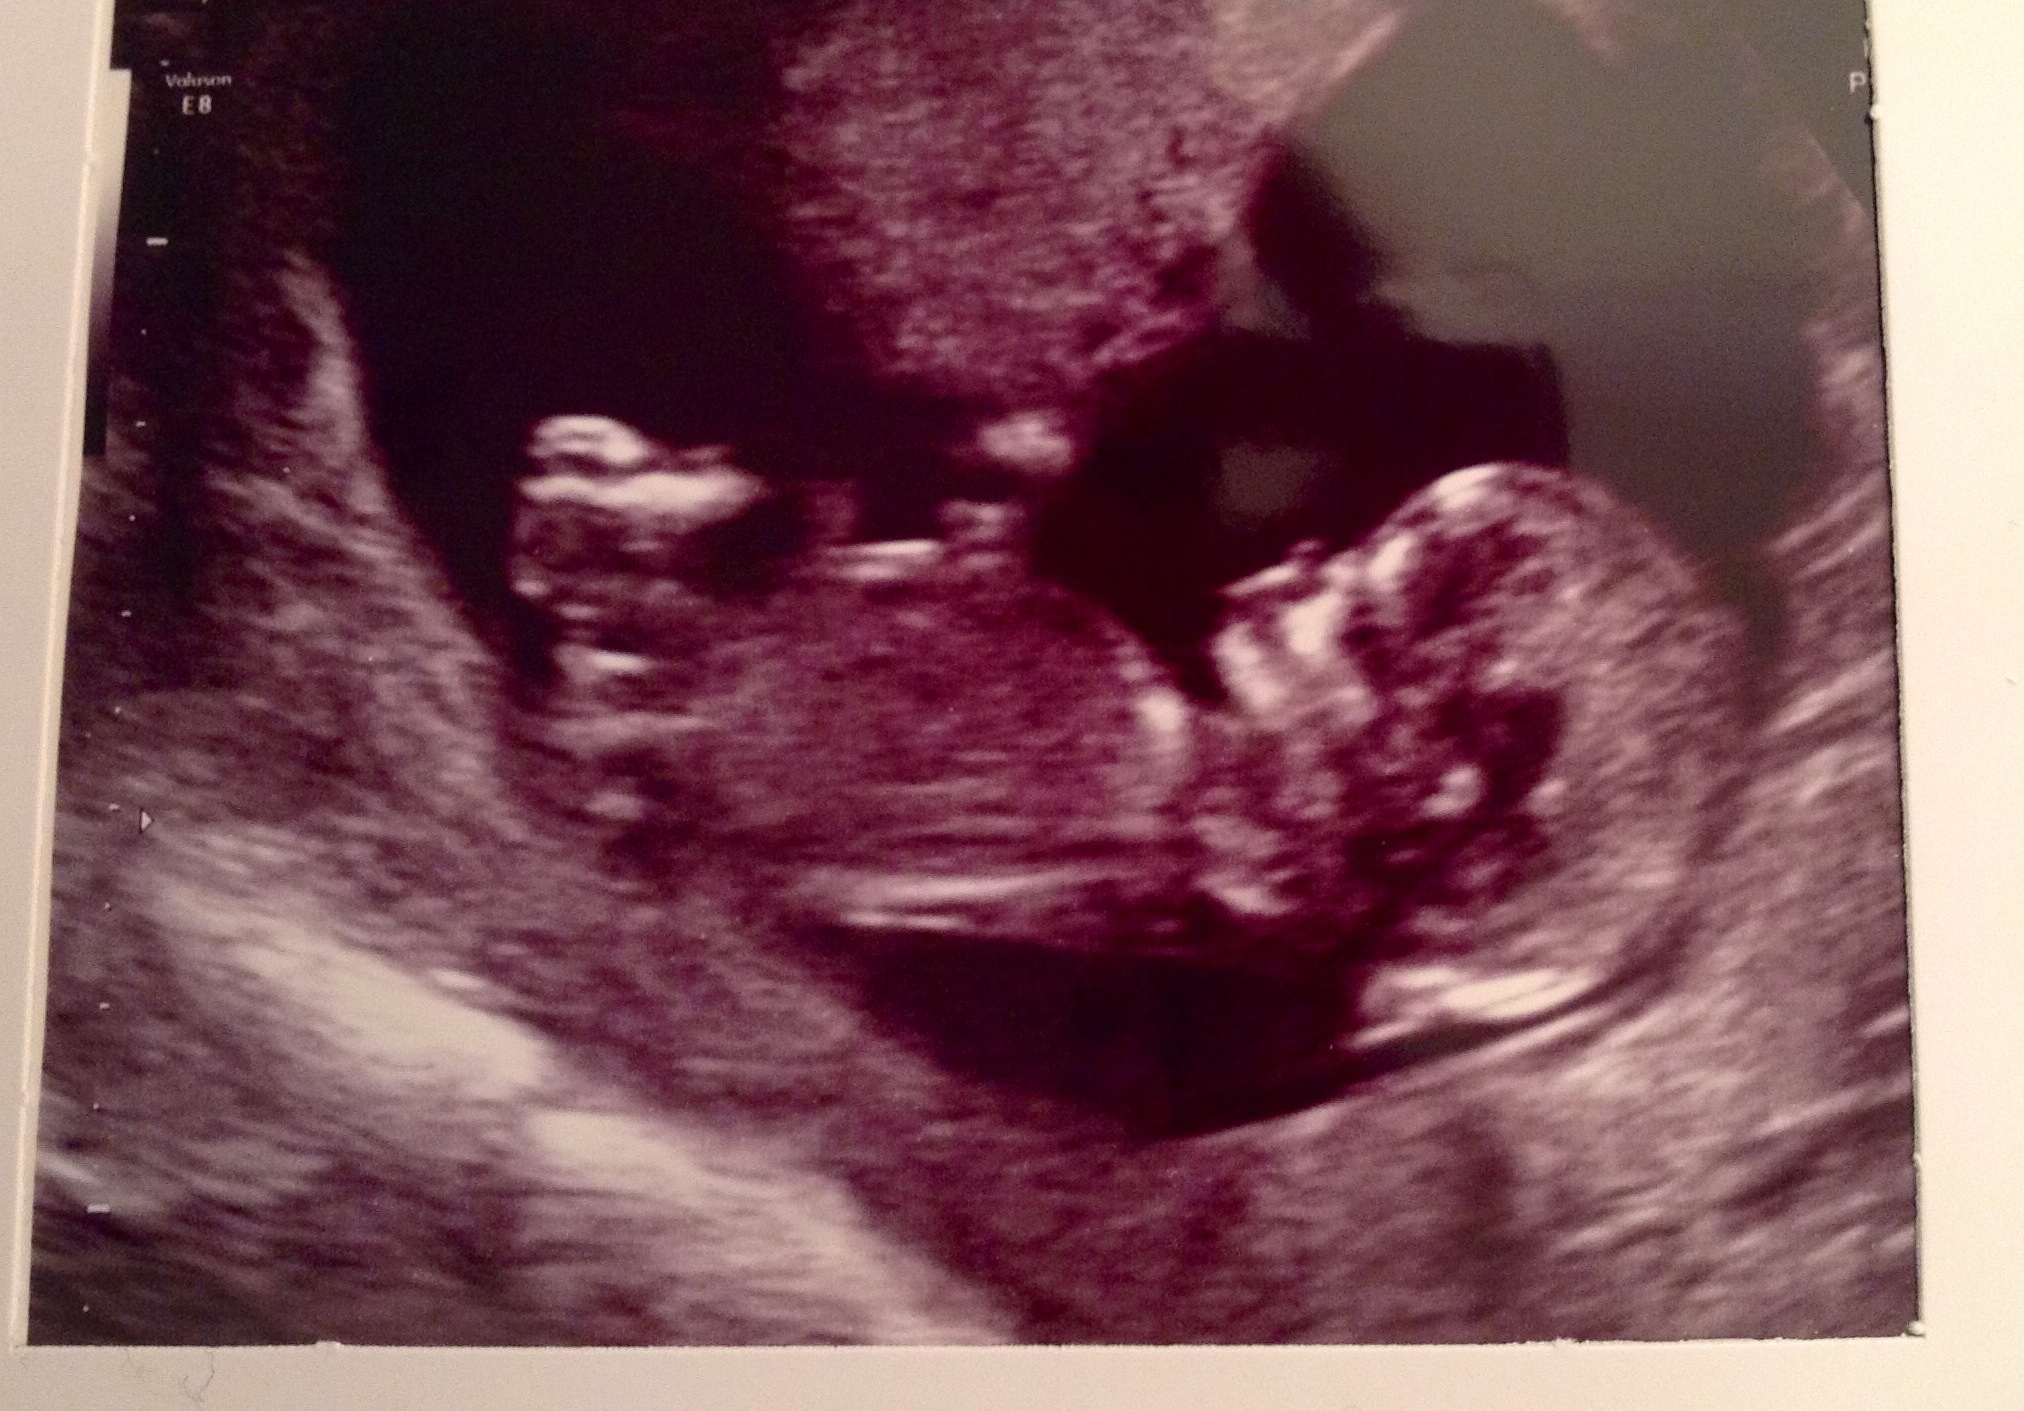

im 17+4 potty shot defo boy !!!!Attachment 8375

this is my 12 week scan to show girl looking skull can be a boy every1 thought girl.Attachment 8376